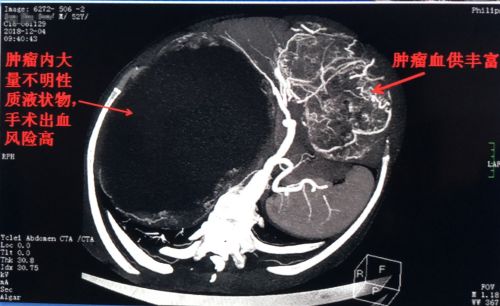

ct上可以看到巨大的肿瘤内充满囊液。

进一步检查发现,陈伟雄右肝有一个24厘米的囊性肿块,左肝一个20厘米的实性肿块,下腹部还有一个5cm的实性肿块。首席专家吴金术教授率彭创、易为民、郭超等组成的专家团队充分评估手术风险,精心制定完善的手术计划后,于12月13日为患者施行手术。

术中发现,右肝巨大囊性肿瘤基本占据整个腹腔,且坏死出血。在切除腹壁小肿块和左肝外叶巨大肿瘤腾出空间后,将右肝囊性肿瘤内的陈旧性出血抽出2500毫升。这时,右肝肿瘤明显缩小,再进行前入路解剖性右半肝切除。采取分组手术完整切除肿瘤,三个肿瘤共计7.13公斤,其中左肝实质肿块约20×18×13cm大小,右肝囊性肿块24×20×17cm大小,犹如一对“双胞胎”。